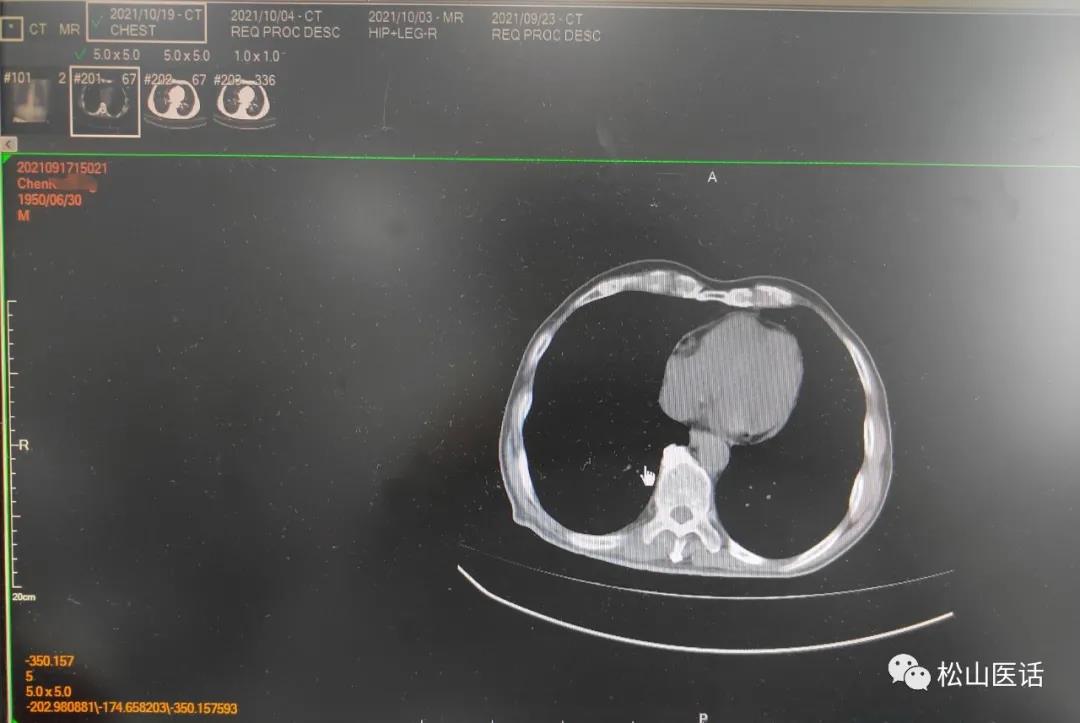

于是10月14号就停用两性霉性B,单独应用伏立康唑抗真菌治疗,并与万古霉素联合应用直到10月20号时体温恢复已10天,于是复查肺部CT与10月4号肺部CT比较,

原双侧胸腔积液已完全吸收、左肺下叶完全复张。

表明肺部感染、骨髓感染彻底控制,本次从8月初开始的发热终于在10月中旬得以控制。

骨髓细菌感染+肺部真菌感染成为持续高热的罪魁祸首。